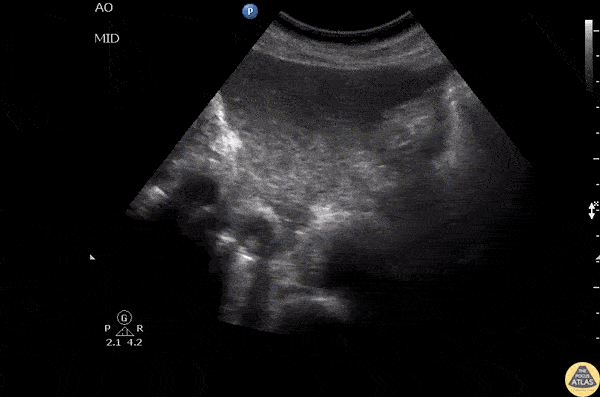

Vascular - IVC Thrombus

This patient presented with bilateral LE swelling and negative DVT scans. Doppler waveform showed results concerning for proximal obstruction. Transverse abdominal scan shows a thrombus within the inferior vena cava. Image courtesy of Robert Jones DO, FACEP @RJonesSonoEM Director, Emergency Ultrasound; MetroHealth Medical Center; Professor, Case Western Reserve Medical School, Cleveland, OH View his original post here